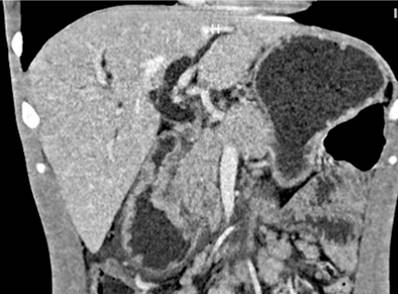

Se trata de un paciente masculino de 29 años de edad, natural de Venezuela y procedente de Santander de Quilichao (Cauca, Colombia), que trabajaba como domiciliario. Desde hace 4 meses presentaba dolor en el epigastrio, emesis de contenido alimentario y bilioso, deposiciones blandas de color amarillo, astenia y adinamia. Desde hace 10 días notó un tinte ictérico no asociado a acolia o coluria y desde hace 2 días refirió un único pico febril no cuantificado, además de la pérdida de 16 kg de peso en los últimos 4 meses. En el interrogatorio negó antecedentes clínicos. En el examen físico de ingreso los signos vitales se encontraban dentro de los rangos de normalidad, las escleras ictéricas, el abdomen doloroso a la palpación del epigastrio sin signos de irritación peritoneal y con adenopatías inguinales bilaterales móviles no dolorosas. Los paraclínicos sanguíneos mostraban en suero reacción en cadena de la polimerasa (PCR): 238 mg/dL, bilirrubina total: 8,5 mg/dL, bilirrubina directa: 4,9 mg/dL, fosfatasa alcalina: 2013 UI/L, amilasa: 64 U/L, alanina-aminotransferasa (ALT): 324 UI/L, aspartato-aminotransferasa (AST): 168 UI/L y el cuadro hemático con leucocitos: 10 700/μL, hemoglobina: 12,3 g/dL, hematocrito: 37,7%, plaquetas: 467 000/μL y neutrófilos: 79,8%. La ecografía de abdomen total señalaba una dilatación de la vía biliar intra- y extrahepática con un colédoco de 11 mm, sin lesiones en el parénquima hepático y múltiples adenopatías peripancreáticas. Posteriormente, se ordenó una tomografía simple y contrastada del abdomen que confirma una masa a nivel periampular asociada con múltiples adenopatías mesentéricas y retroperitoneales (Figura 1).

Figura 1 Tomografía de abdomen simple y contrastada: dilatación de la vía biliar intra- y extrahepática con un colédoco de 14 milímetros, el páncreas con ligera dilatación del conducto Wirsung y pérdida de los contornos a nivel de la cabeza. En la región periampular había un engrosamiento parietal circunferencial concéntrico con refuerzo luego de la administración de contraste y múltiples adenopatías mesentéricas, retroperitoneales, lateroaórticas e intercavoaórticas. Fuente: Departamento de Radiología, Hospital Universitario del Valle.